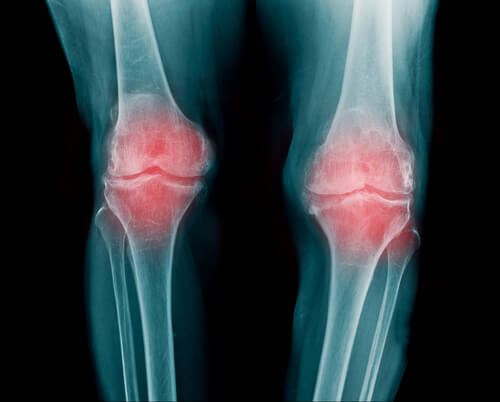

Uma articulação é uma área em que se encontram as extremidades de dois ou mais ossos, ou um osso e uma cartilagem. Graças a elas, o corpo pode se mover, são elas que permitem flexionar e girar as pernas, braços e costas.

Entre os ossos que formam a articulação, há um tecido elástico flexível, a cartilagem articular. A cartilagem evita o atrito entre os ossos, atuando como um sistema de amortecimento.

A articulação é rodeada por um “bolsa articular” que sustenta todo este sistema. Essa bolsa é reforçada por ligamentos que impedem que as articulações se danifiquem facilmente.

Segundo informações obtidas da Biblioteca Nacional de Medicina dos Estados Unidos, é uma inflamação na articulação e pode aparecer em diferentes partes do corpo. Geralmente, as mais afetadas são as dos dedos, braços e joelhos.